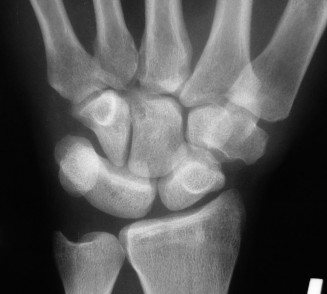

Radiographic evaluation requires specific, non-standard views. A standard PA and lateral of the wrist will often obscure the pisiform due to bony overlap. Therefore, a 30-degree supinated lateral view or a carpal tunnel view is essential to profile the pisiform and evaluate the pisotriquetral joint space. In cases of delayed union or subtle comminution, a fine-cut non-contrast Computed Tomography (CT) scan provides invaluable three-dimensional mapping. For the elderly patient presenting with progressive, non-traumatic base of thumb pain, standard radiographs must include a Robert's view (a true AP of the first CMC joint) and stress views to evaluate the degree of radial subluxation. The image above clearly demonstrates advanced 1st CMC arthritis, characterized by complete loss of joint space, subchondral sclerosis, and osteophyte formation, confirming the diagnosis.